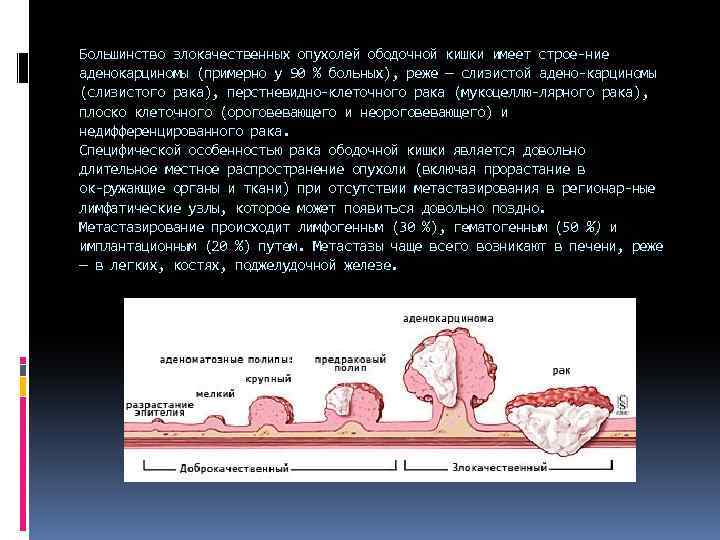

Большинство злокачественных опухолей ободочной кишки имеет строе ние аденокарциномы (примерно у 90 % больных), реже — слизистой адено карциномы (слизистого рака), перстневидно клеточного рака (мукоцеллю лярного рака), плоско клеточного (ороговевающего и неороговевающего) и недифференцированного рака. Специфической особенностью рака ободочной кишки является довольно длительное местное распространение опухоли (включая прорастание в ок ружающие органы и ткани) при отсутствии метастазирования в регионар ные лимфатические узлы, которое может появиться довольно поздно. Метастазирование происходит лимфогенным (30 %), гематогенным (50 %) и имплантационным (20 %) путем. Метастазы чаще всего возникают в печени, реже — в легких, костях, поджелудочной железе.